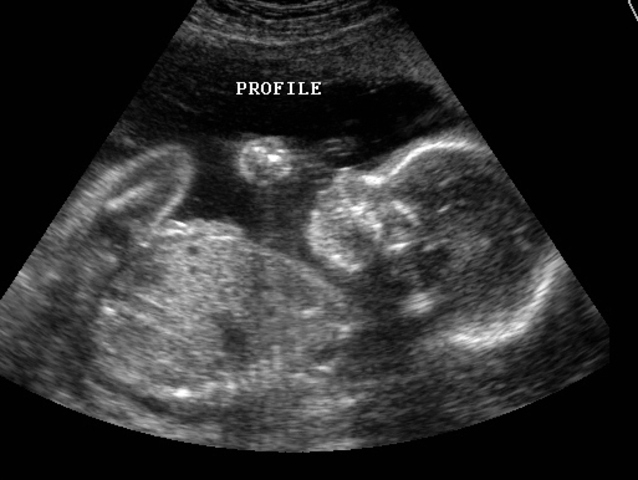

• Level 1 U/S 18-22 weeks

Level 1 U/S 18-22 weeks

Anatomy scan at 18-22 weeks

• BPP at >32 weeks

BPP at >32 weeks

BPP: at greater than 32 weeks -NST (20-30 min)

-U/S